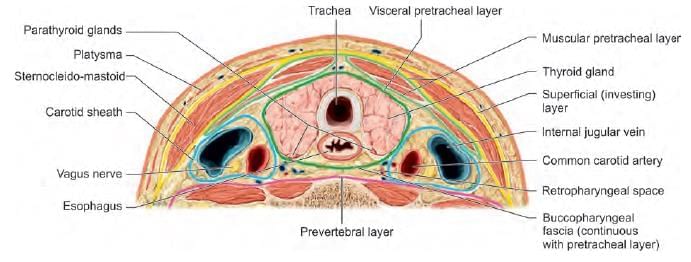

Which of the following nerve is least injured in thyroid surgery? (AIIMS June 2020)

The upward extension of thyroid swelling is prevented by which of the following structure attached to thyroid cartilage? (NEET-PG 2020)

Inferior thyroid artery supplies: (INI-CET Nov 2021)

A. Oesophagus

B. Thyroid

C. Parathyroid

D. Thymus